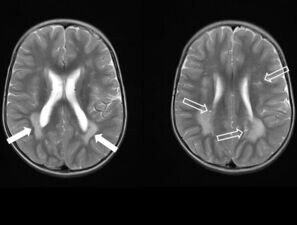

Ein 2-jähriger Junge mit Makrozephalie und Leukenzephalopath...

Ein Junge wird für eine zweite Meinung zu einer unklaren Leukenzephalopathie vorgestellt. Bei der Untersuchung fallen eine Makrozephalie, Pigmentflecken auf der Glans penis und narbige Veränderungen am rechten Fußrücken nach Entfernung einer "Warze" auf. Wie lautet Ihre Verdachtsdiagnose?